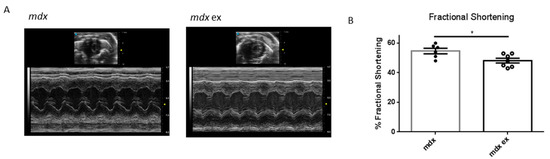

3.5. The Exercise Protocol Alters Mdx Heart Function

| End-Diastolic Diameter [mm] | End-Systolic Diameter [mm] | Anterior Wall Thickness [mm] | Posterior Wall Thickness [mm] | Fractional Shortening [%] | Heart Rate (bpm) | Heart/Body Weight [mg/g] | |

|---|---|---|---|---|---|---|---|

| mdx | 2.77 ± 0.07 | 1.27 ± 0.08 | 1.13 ± 0.04 | 1.08 ± 0.02 | * 54.42 ± 1.89 | 452 ± 25.2 | 7.0 ± 0.24 |

| mdx ex | 2.76 ± 0.06 | 1.44 ± 0.03 | 1.06 ± 0.04 | 1.11 ± 0.03 | * 48.14 ± 1.61 | 443 ± 43.8 | 6.8 ± 0.17 |